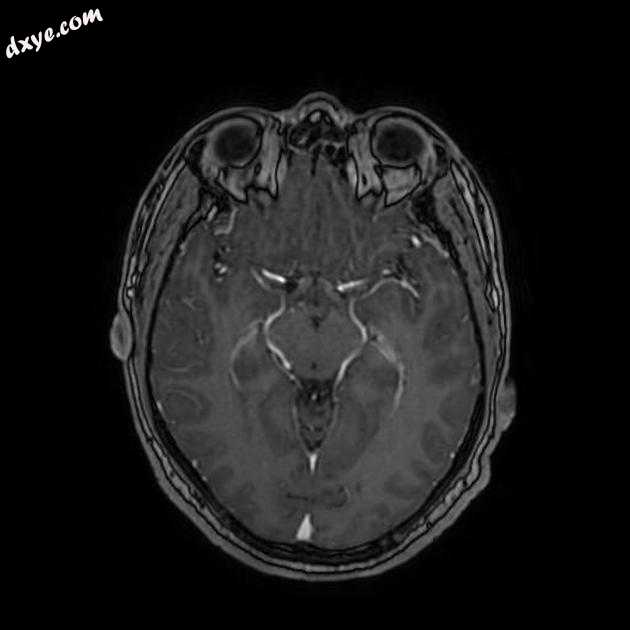

Axial FLAIR

MRI 序列显示右侧颈内动脉的部分血栓囊状动脉瘤位于 C6/7 节段的交界处,大小为 11 x 7 毫米,颈部为 2.5 毫米,压迫动眼神经 (III) 的相邻节段,在 T1 上清晰可见和 FIESTA 序列。

位于 C6/7 交界处的右侧颈内动脉部分血栓囊状动脉瘤的 MRI 特征,压迫同侧动眼神经 (III)。